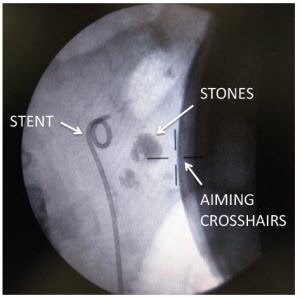

1. PCNL with Holmium Laser (Laser Mini Perc)

Percutaneous nephrolithotomy (PCNL) is a surgical procedure to remove stones from the kidney by a small puncture wound (up to about 1 cm) through the skin. It is most suitable to remove stones of more than 2 cm in size and which are present near the pelvic region. It is usually done under general anesthesia or spinal anesthesia. A retrograde pyelogram is done to locate the stone in the kidney. With a small 1 centimeter incision in the loin, the percutaneous nephrolithotomy (PCN) needle is passed into the pelvis of the kidney. The position of the needle is confirmed by fluoroscopy. A guide wire is passed through the needle into the pelvis. The needle is then withdrawn with the guide wire still inside the pelvis. Over the guide wire the dilators are passed and a working sheath is introduced. A nephroscope is then passed inside and small stones taken out. In case the stone is big it may first have to be crushed using ultrasound probes and then the stone fragments removed. The most difficult portion of the procedure is creating the tract between the kidney and the flank skin. Most of the time this is achieved by advancing a needle from the flank skin into the kidney, known as the 'antegrade' technique. A 'retrograde' technique has recently been updated wherein a thin wire is passed from inside the kidney to outside the flank with the aid of a flexible ureteroscope. This technique may reduce radiation exposure for patient and surgeon.

It is a keyhole surgery for removal of kidney stones in which instruments with small diameter are used for smaller kidney punctures. Laser, pneumatic and ultrasound devices are used in the process to fragment stones and there is very less bleeding in the process. With high energy new generation Auriga XL Holmium Laser machine, even hard and large stones are fragmented quickly with less bleeding. We are one of the pioneers in offering the PCNL treatment in India since 2008 and have over 1000 successful cases to our credit. Dr Paruliya has vast experience in simple and complex PCNL in single kidney, large and multiple stones, bilateral PCNL in single sitting, paediatric PCNL, stones with renal impairment with excellent results – high rate of complete clearance, minimal morbidity.